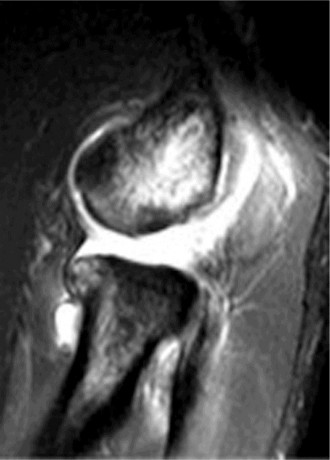

A 24-year-old, male athlete sustains an anterior shoulder dislocation. His MRI is shown in Figure 2–32.

Figure 2–32

Which of the following ligaments is injured?

Discussion

The correct answer is (A). The MRI demonstrates an HAGL lesion. The MR arthrogram shows fluid extending down the medial humerus and is indicative of an HAGL. Most commonly, with an anterior dislocation, the anterior band of the inferior glenohumeral ligament is torn. With a posterior dislocation, the posterior band is torn creating a reverse HAGL. The ligament tends to tear off the humeral side. These are important injuries to identify as arthroscopic labral repair and capsular shift may be unsuccessful without concomitant repair of the HAGL lesion. Many authors advocate an open approach to repair an HAGL lesion.